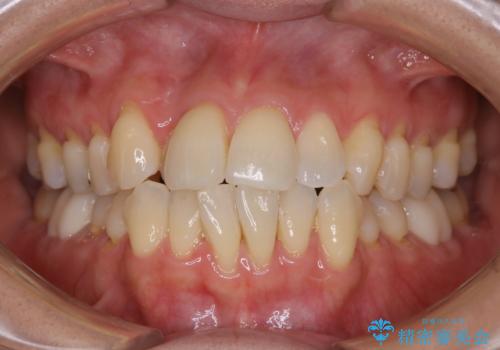

ワイヤー矯正中のPMTC

- ワイヤー矯正中に装置の周りの着色が気になるとのことで来院されました。PMTC30分コースを行いました。

ワイヤー矯正中も、歯の表面に着色(ステイン)が付着することがあります。着色(ステイン)が付着したままだと審美的な問題以外にも、虫歯を発見しずらいことや、細菌が繫殖しやすくなることがあります。クリーニングを行うことで、虫歯や歯周病予防に効果的だったり、もちろん見た目も審美的です。クリーニング後には、汚れが取り除かれ、お口の中がスッキリ・爽快感で気持ちがよくなります。矯正中も定期的にPMTCを行うことが大切です。